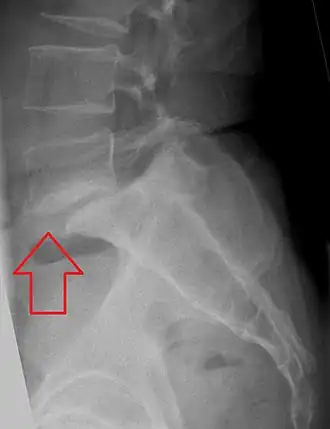

Anterolistesis L5/S1 -

Anterolistesis L5/S1. Flecha azul pars interarticularis normal. La flecha roja es una ruptura en pars interarticularis -

Anterolistesis L5/S1